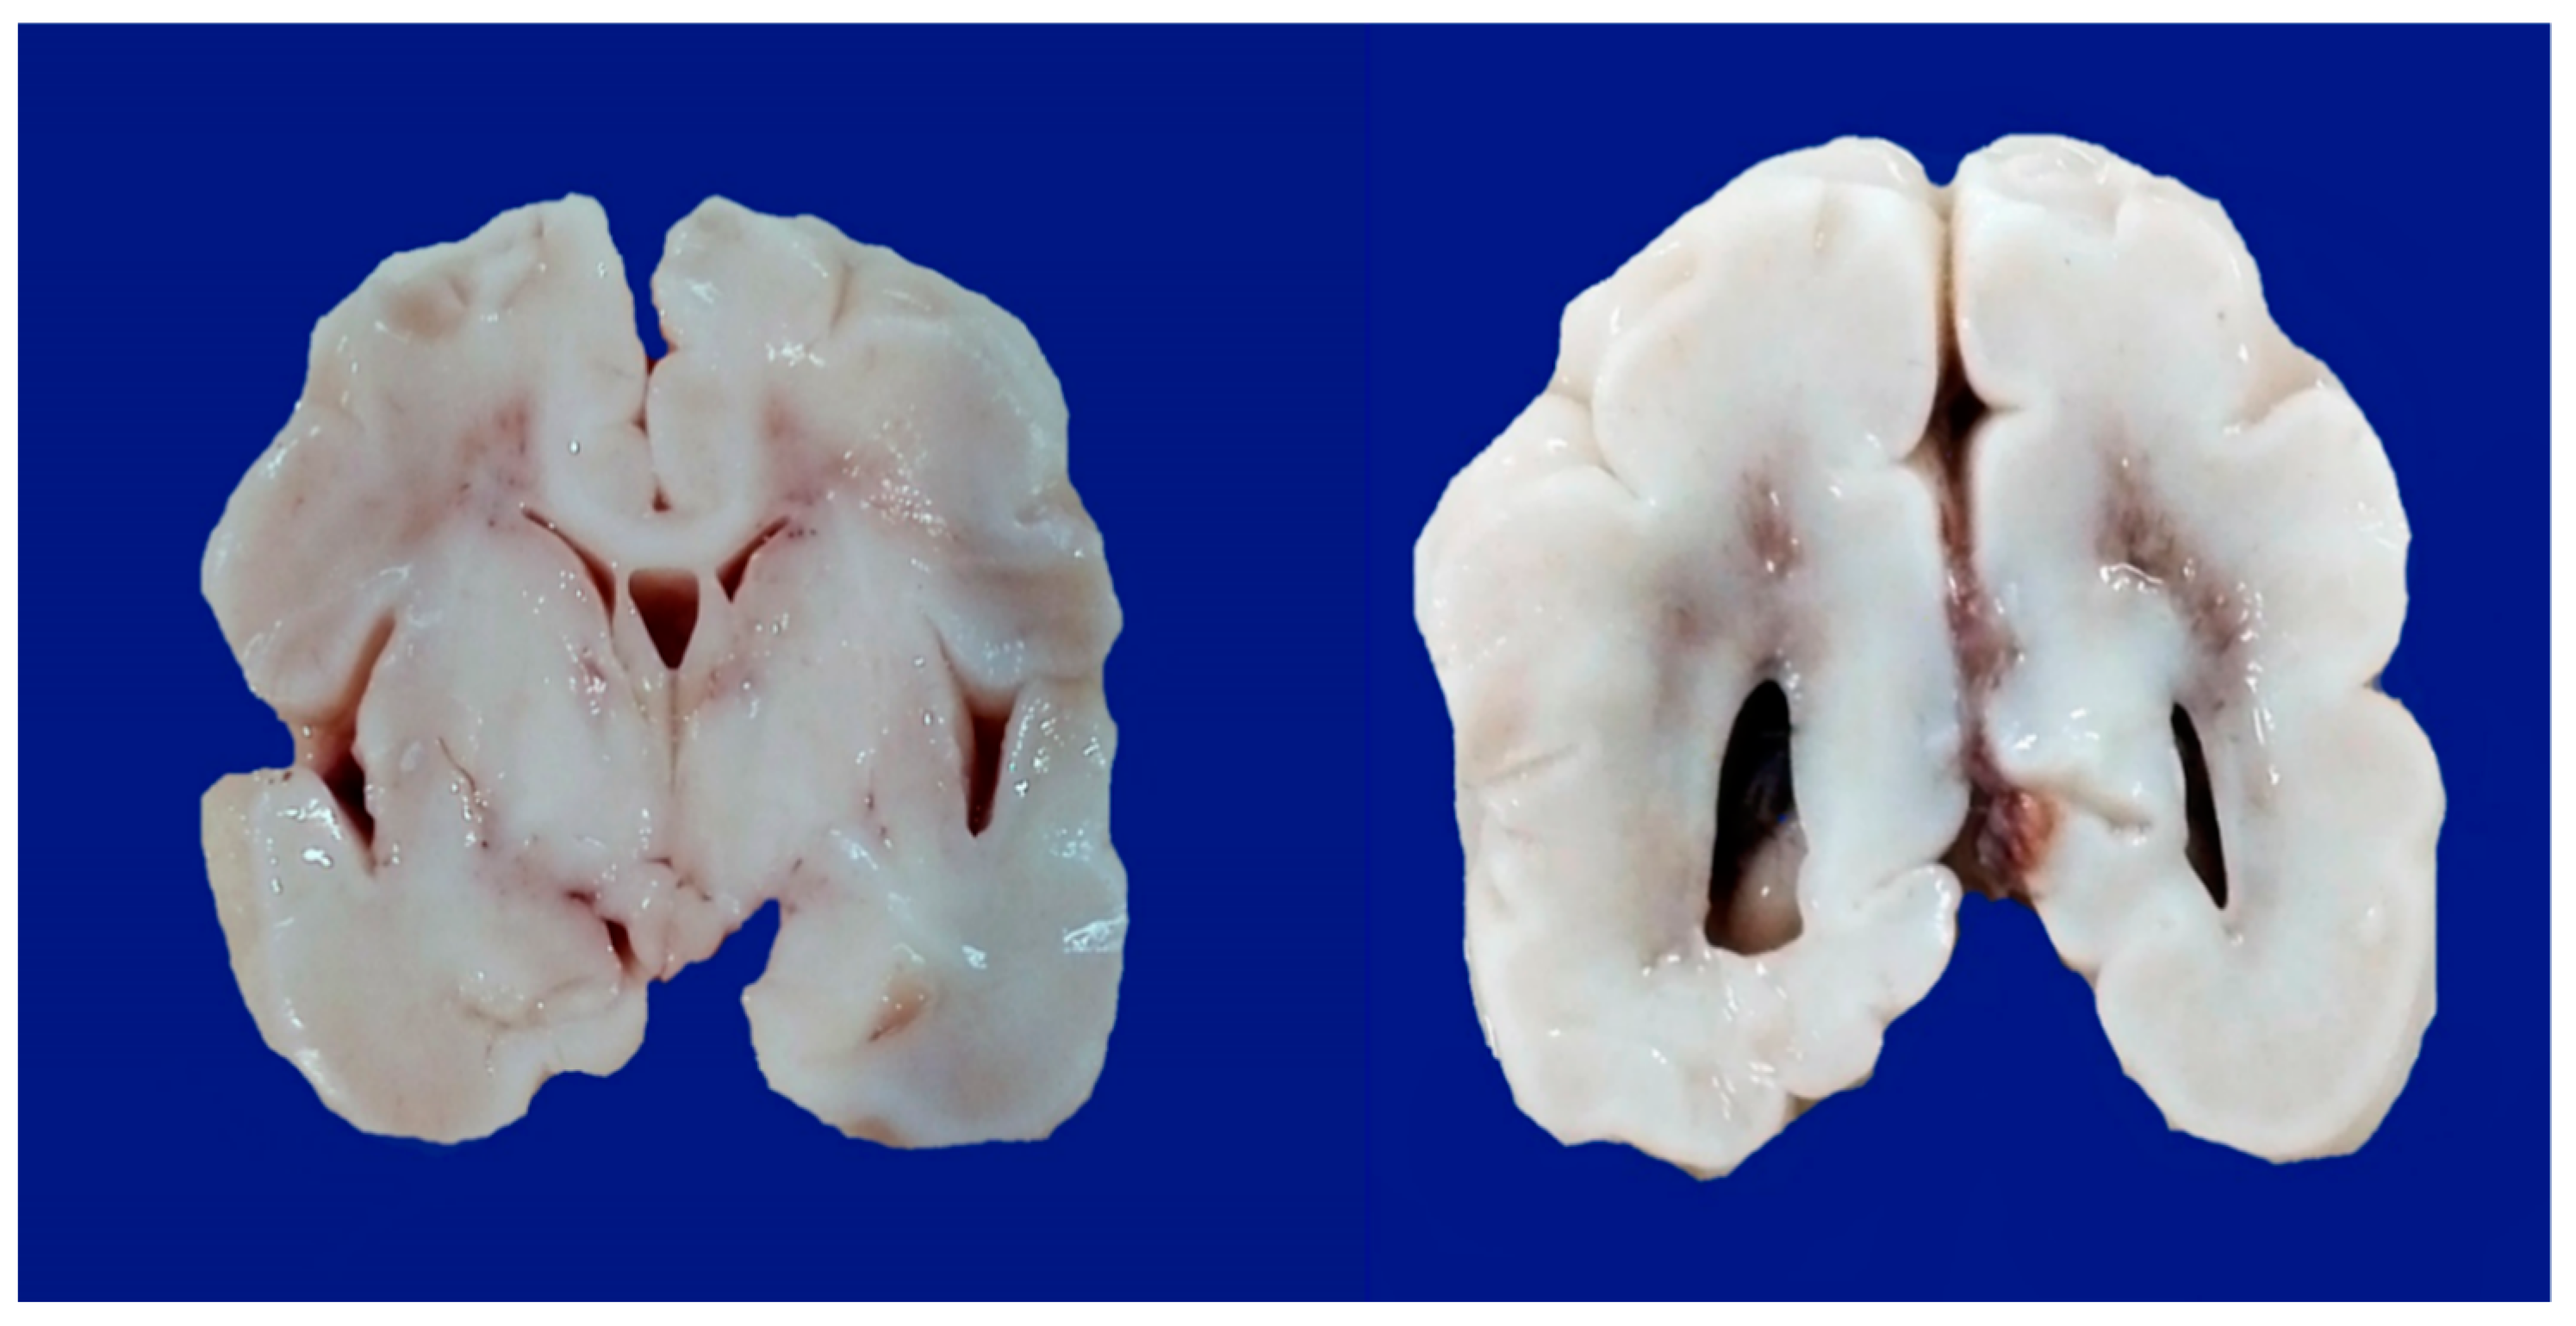

- Parasagittal injury of the cerebral cortex, in subcortical white matter in the lateral convection of the superior-medial orientation, in the posterior–anterior direction.

- Periventricular leukomalacia with necrosis in the subcortical white matter of the hemisphere, including descending motor fibers, optical radiations, and association fibers.

- Focal and multifocal necrotic ischemia in the cerebral cortex and subcortical necrosis in white matter, mainly unilateral with a vascular distribution.